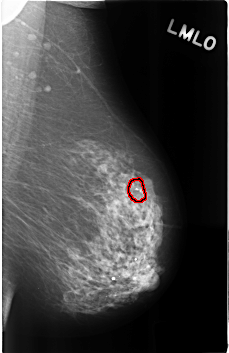

ics_version 1.0 filename C-0287-1 DATE_OF_STUDY 9 1 1995 PATIENT_AGE 89 FILM FILM_TYPE REGULAR DENSITY 2 DATE_DIGITIZED 4 8 1998 DIGITIZER LUMISYS LASER SEQUENCE LEFT_CC LINES 4592 PIXELS_PER_LINE 2960 BITS_PER_PIXEL 12 RESOLUTION 50 OVERLAY LEFT_MLO LINES 4584 PIXELS_PER_LINE 2976 BITS_PER_PIXEL 12 RESOLUTION 50 OVERLAY RIGHT_CC LINES 4568 PIXELS_PER_LINE 2928 BITS_PER_PIXEL 12 RESOLUTION 50 NON_OVERLAY RIGHT_MLO LINES 4600 PIXELS_PER_LINE 2904 BITS_PER_PIXEL 12 RESOLUTION 50 NON_OVERLAY |

FILE: C_0287_1.LEFT_MLO.OVERLAY TOTAL_ABNORMALITIES 1 ABNORMALITY 1 LESION_TYPE CALCIFICATION TYPE PLEOMORPHIC DISTRIBUTION CLUSTERED ASSESSMENT 4 SUBTLETY 5 PATHOLOGY BENIGN TOTAL_OUTLINES 1 BOUNDARY |